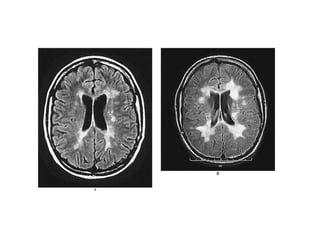

MIELINA-MIELINIZACIÒN La mielinaes la base estructural de la teoría saltatoria del impulso nervioso El segmento de revestimiento forma el internodo de Ranvier, el espacio entre dos de estos internodos es el nodo de Ranvier (sitio de regeneración del impulso nervioso). Existen varios tipos de enfermedades desmielinizantes Afectan a los oligodendrocitos y a la mielina no al axon a. Autoinmunes Esclerosis múltiple-Guillan Barre b. Hereditarias adrenoleucodistrofia, ligada al X, en el suero ácidos grasos de cadena corta, daño en el gen que codifica las proteínas de los peroxisomas c. Metabólicas déficit de B12, mielinolisis pontina, en pacientes a quienes se les corrige hiponatremias por alcoholismo o por desnutrición d. Inducidas por virus encefalopatía focal progresiva, en el VIH sida los oligodendrocitos son invadidos por virus oportunistas e. Quimio-Rtpia